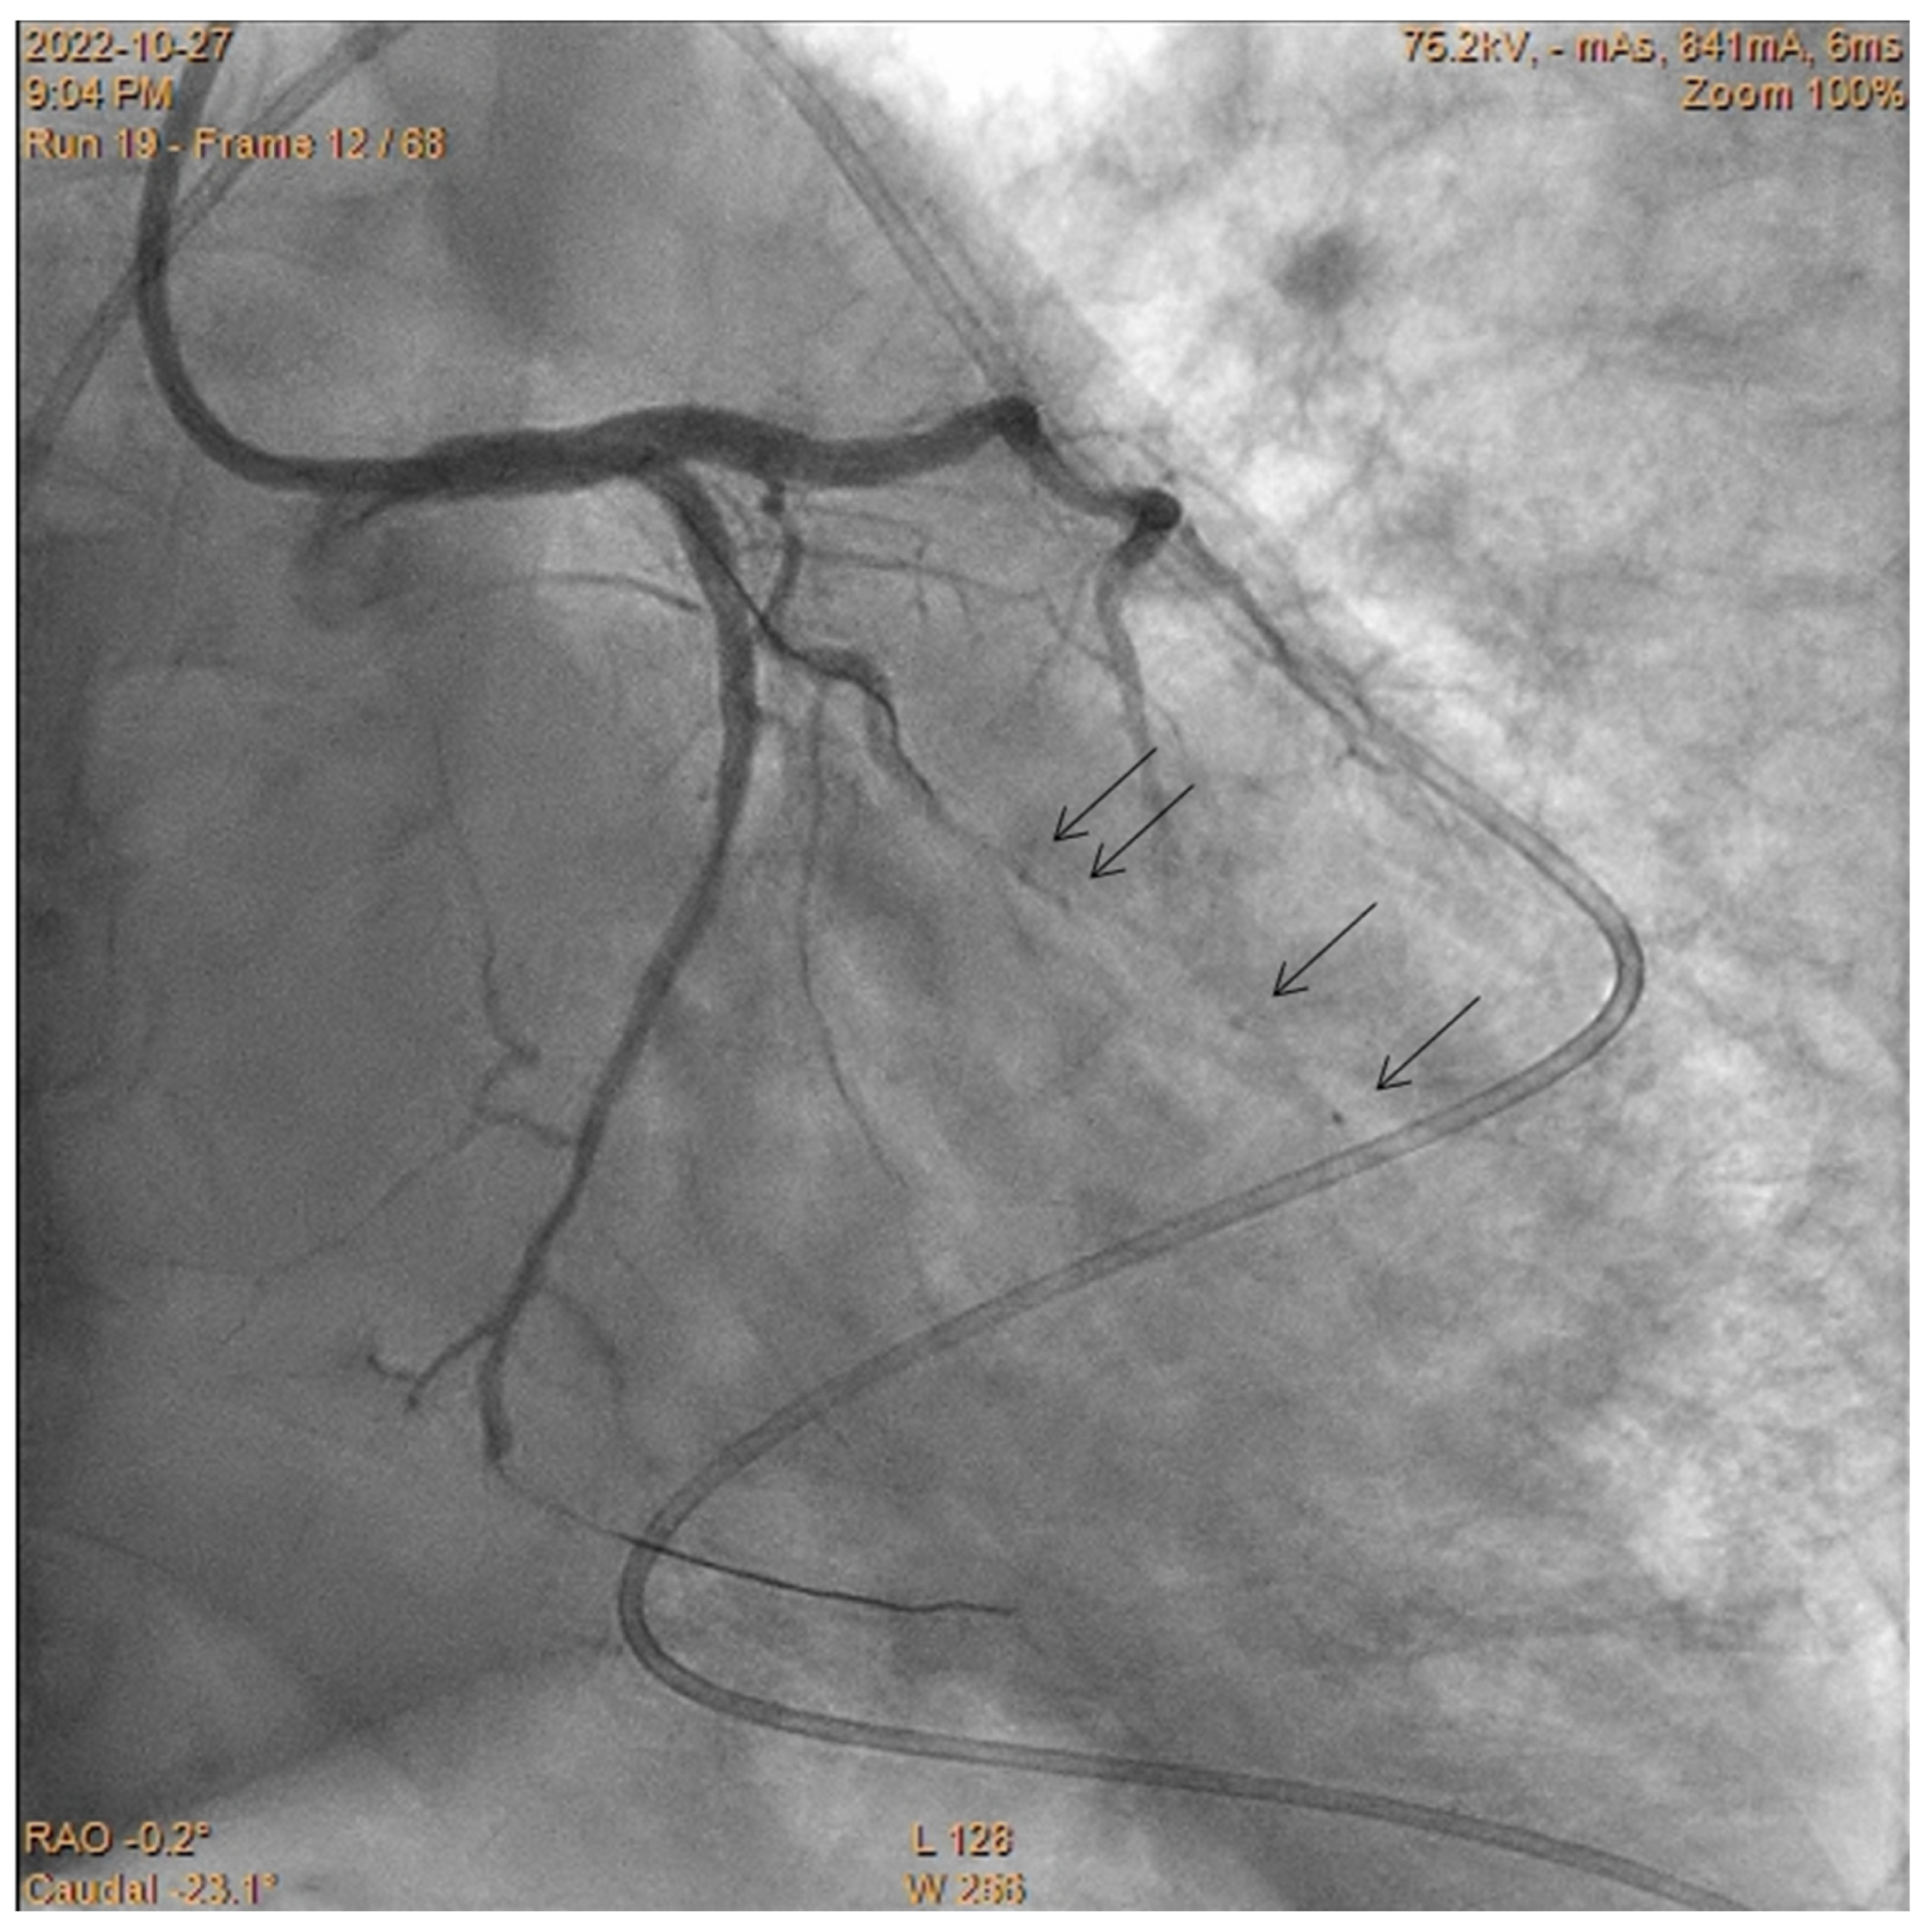

Embolization of Perforated Coronary Artery with a Fragment of Balloon Catheter (Cut Balloon Technique)—Multicenter Study

2. Methods

3. Results